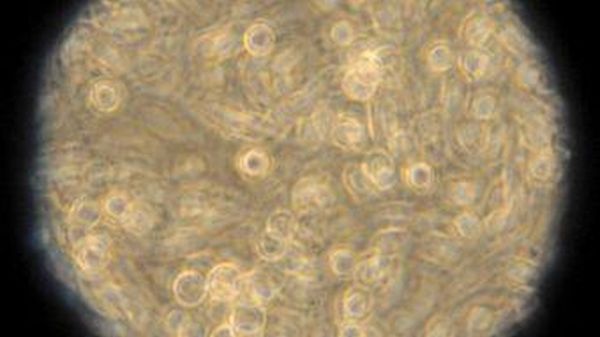

Scienza/ Test urine può rivelare propensione tumore prostata Livello proteina Msmb più basso in uomini predisposti a tumore